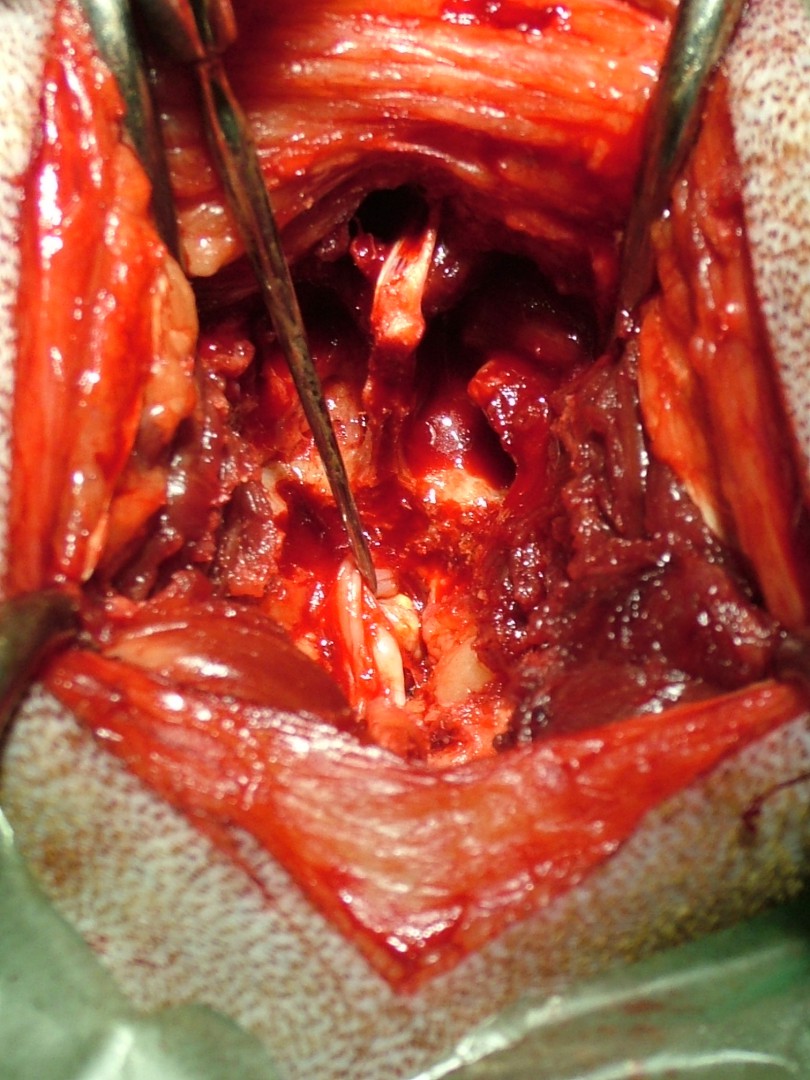

Ám az öröm nem tartott sokáig. Szürke Farkas 5 nappal a műtéte után a kocsiba ugrás közben felsírt és mire a rendelőbe ért a fájdalomtól fel sem tudott állni. A kórházi felvételt követően fájdalomcsillapítók, antibiotikumok adását kezdtük meg és mivel a műtéti területen klinikai és RTG vizsgálattal sem találtunk a fájdalmat magyarázó elváltozást Kaposvárra, MRI vizsgálatra vittük. 2 nappal később meglepődve olvastuk az eredményt: a 9.-10.( Th9-Th10 ) hátcsigolyák valamint a 7 ágyéki és az 1. keresztcsonti csigolyák ( L7-S1 ) közötti porckorong gyulladásos elváltozása ( ld.: discospondylitis ) mellett a 11. és a 12. hátcsigolya magasságában ( Th 11-Th12 ) a gerincvelőt összenyomó daganatos elváltozás volt látható. Mivel a porckorongok gyulladása megmagyarázta a gerinctájéki fájdalmasságot, annak kezelése és a fájdalom további csillapítása volt az első teendőnk. Néhány nappal a fájdalom enyhülését követően a gerincvelőt összenyomó daganatot műtétileg eltávolítottuk. Ezt követően Szürke Farkas még további 60 napot töltött a kórházban. A lábadozása napról napra szépen alakult. Betegségének 90. napján hazaadtuk és a gyógyszerek további adása mellett állapotát hetente ellenőriztük.